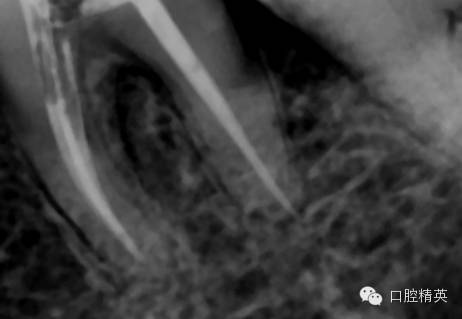

tf镍钛锉预备至30#06锥度(虽然根尖区域的预备应该在35#~40#)但我认为这不是根尖周炎,所以仅仅预备到30#,大量次氯酸钠荡洗根管,根充还是用的iroot糊剂和热牙胶,我用的是思博安的热牙胶,很多同行和我说,相比韩国的产品思博安的成本太高了,但思博安的牙胶是 β象限的,低温时的流动性更好,更容易进入狭窄部位和侧支根管,所以我认为,相对与更好的治疗效果,成本并不重要。

近中根管的侧枝清晰可见

![36的一次性根充]()